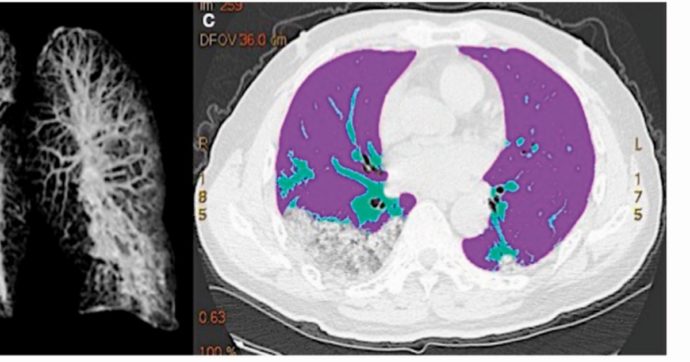

La polmonite interstiziale derivante dal Covid-19 provoca diverse “lesioni ai lobi superiore e inferiore”, “versamento pleurico” e, soprattutto, “l’allargamento del 5-10% dei vasi sanguigni” che trasportano il sangue dal cuore ai polmoni. Ma questi danni “non sembrano essere permanenti”, come spiegato al Fatto dal direttore scientifico dell’istituto Lazzaro Spallanzani di Roma, Giuseppe Ippolito. Proprio l’equipe […]